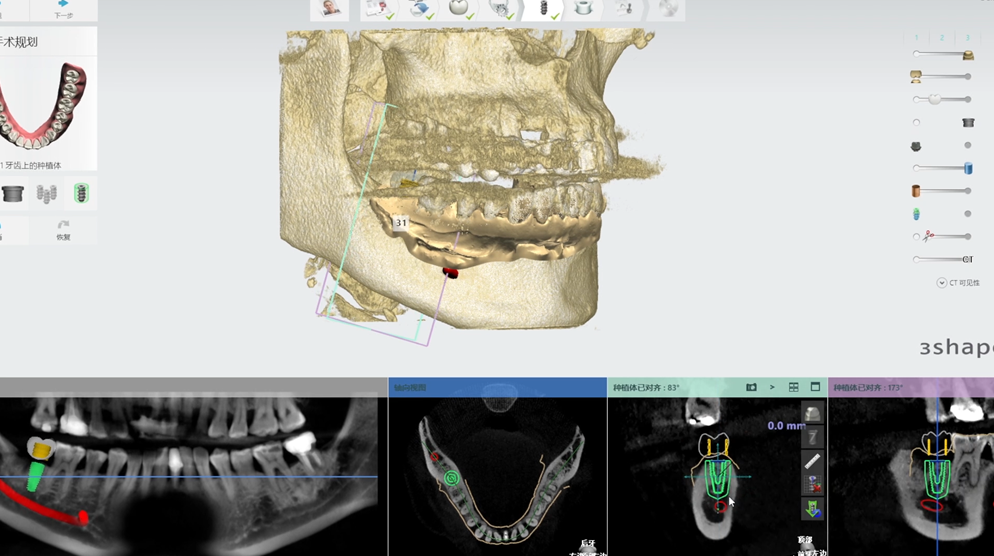

數字化種植牙係利用計算機圖形圖像技術,根據口內CT掃描數據以及光學掃描數據喺計算機上重建患者頜骨立體模型,並以此為基礎,確定患者種植體嵌入位置、數量、種植深度、角度等,生成科學、精准嘅導板設計方案,將種植設計准確地轉化到手術操作中,最後結合患者自身嘅情況製作修復體,完成種植治療。

種植導板適用於大部分種植手術,尤其適用於患者口腔內骨頭情況唔好,醫生手動操作風險較大嘅種植手術。種植導板可以輔助醫生進行快速、准確嘅定位,同時根據CBCT中顯示嘅牙槽骨情況,為醫生規避很多醫療風險,醫患溝通更直觀。